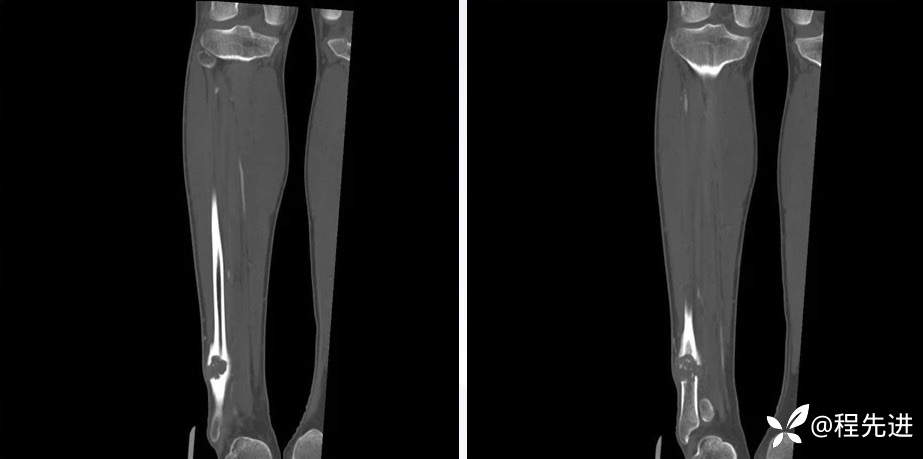

CT平扫、增强动脉期、静脉期

平扫67HU、动脉期81HU、静脉期93HU